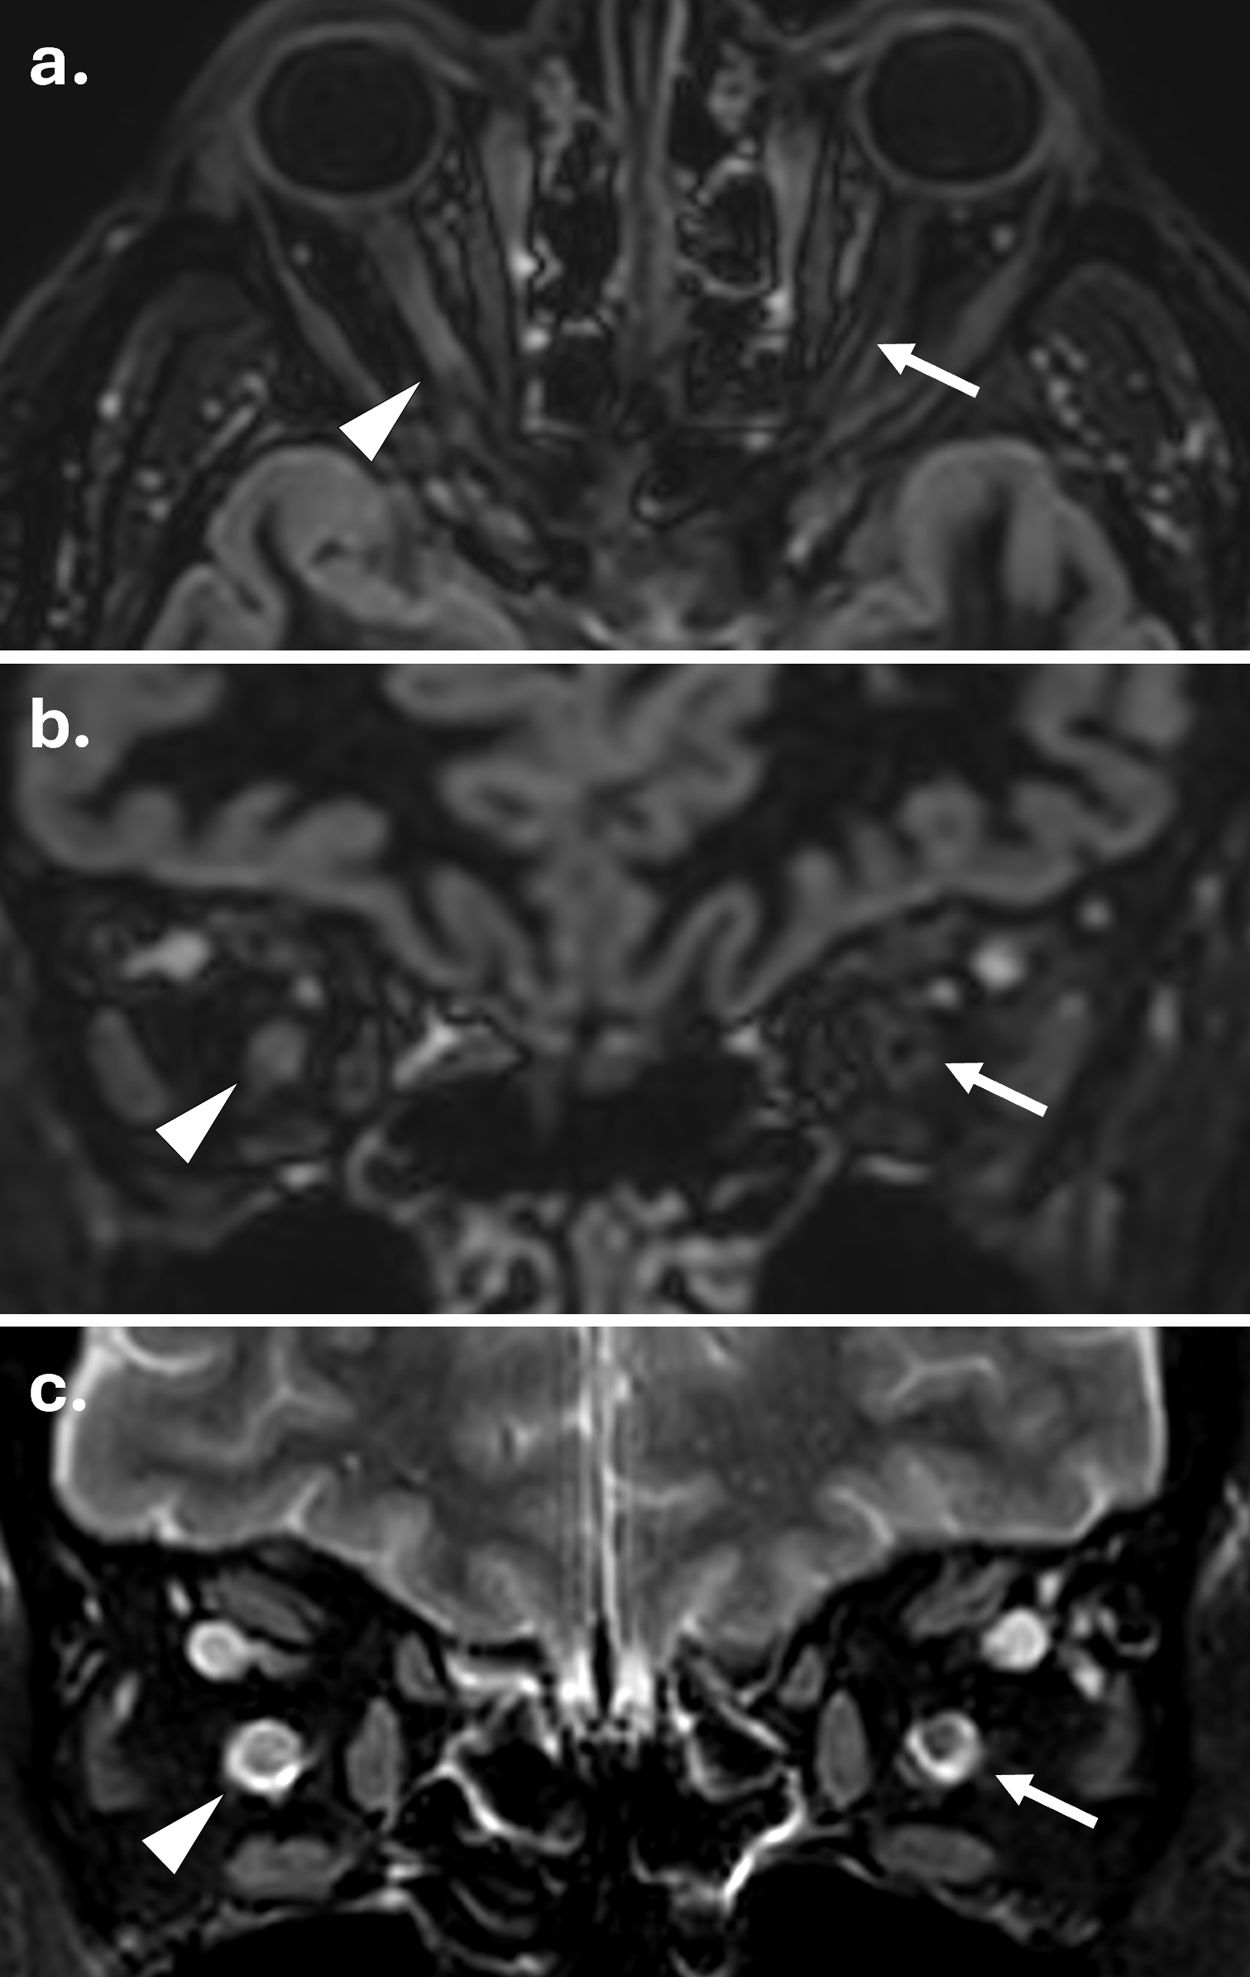

Según los criterios de 2024, la afectación del nervio óptico debe evaluarse principalmente mediante RM, utilizando la tomografía de coherencia óptica y los potenciales evocados visuales como modalidades alternativas11. Cuando se sospecha neuritis óptica aguda, el protocolo de RM recomendado incluye secuencias coronales STIR o T2 con supresión de grasa, e imágenes poscontraste potenciadas T1. Además, las secuencias de doble inversión-recuperación tridimensionales (3D-DIR) pueden mejorar la detección tanto de lesiones sintomáticas como asintomáticas12 (fig. 1).

Detección de lesión del nervio óptico en una persona con esclerosis múltiple mediante secuencias 3D de doble inversión-recuperación (DIR) y T2 con saturación grasa. (a) Reconstrucciones axial y (b) coronal de una adquisición 3D-DIR que demuestran una lesión hiperintensa en el segmento canalicular del nervio óptico izquierdo (flechas). El nervio óptico derecho normal se muestra para comparación (puntas de flecha). (c) Adquisición T2 con saturación grasa al mismo nivel confirma la lesión (flecha) y muestra el nervio óptico contralateral normal (punta de flecha).

Es importante destacar que los hallazgos de la RM ayudan a diferenciar la EM de otras neuropatías ópticas inflamatorias. Las lesiones relacionadas con la EM suelen ser cortas y localizadas anteriormente. La enfermedad asociada a anticuerpos contra la glicoproteína de mielina de oligodendrocitos (MOGAD) se presenta característicamente con lesiones bilaterales longitudinalmente extensas, a menudo simultáneas, con inflamación anterior del nervio óptico y perineuritis, mientras que el trastorno del espectro de la neuromielitis óptica positiva para acuaporina-4 (NMOSD AQP4+) afecta con mayor frecuencia al nervio óptico posterior y al quiasma13.

Diversos desafíos técnicos limitan la imagen del nervio óptico, incluyendo artefactos de movimiento, desplazamiento químico en la interfaz de la grasa orbitaria y efectos de susceptibilidad cerca de los senos paranasales14. La reproducibilidad varía sustancialmente con la optimización de la secuencia y la experiencia del lector15,16. Además, la imagen del nervio óptico ofrece un escaso valor diagnóstico añadido en pacientes asintomáticos, ya que aquellos con lesiones detectables suelen cumplir los criterios DIS a través de la afectación de otras localizaciones anatómicas17. En consecuencia, el consenso MAGNIMS-CMSC-NAIMS de 2024 considera la RM del nervio óptico opcional en casos sin neuritis óptica8.